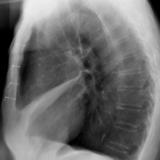

Case 2 Lateral

Date: 02/28/2004

Views: 3393